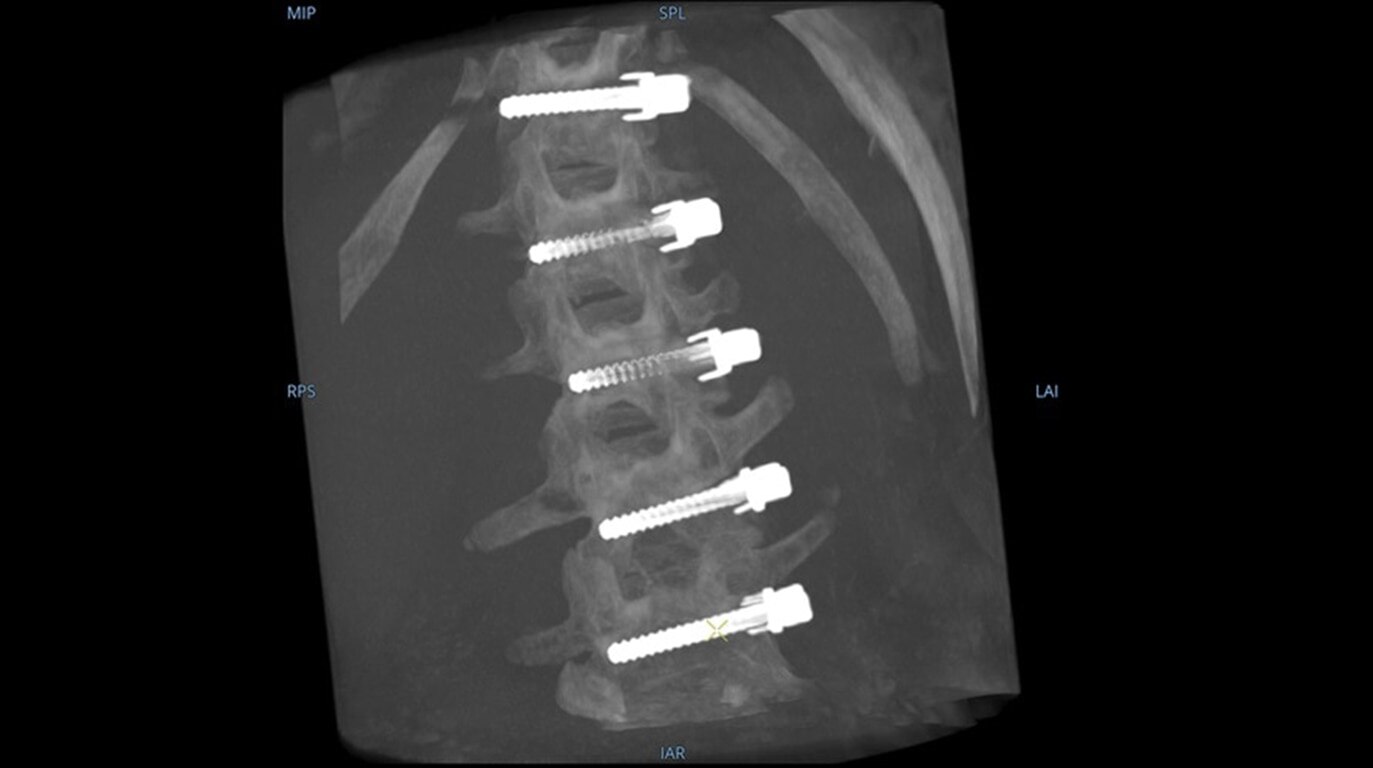

19 cm3 CT-like images presented intraoperatively in minutes

See more levels during a spinal fusion, or more of the pelvis or femur during an orthopedic procedure. With a 19 cm x 19 cm x 19 cm volume, OEC 3D captures a 67% greater volume than other 3D C-arms*.